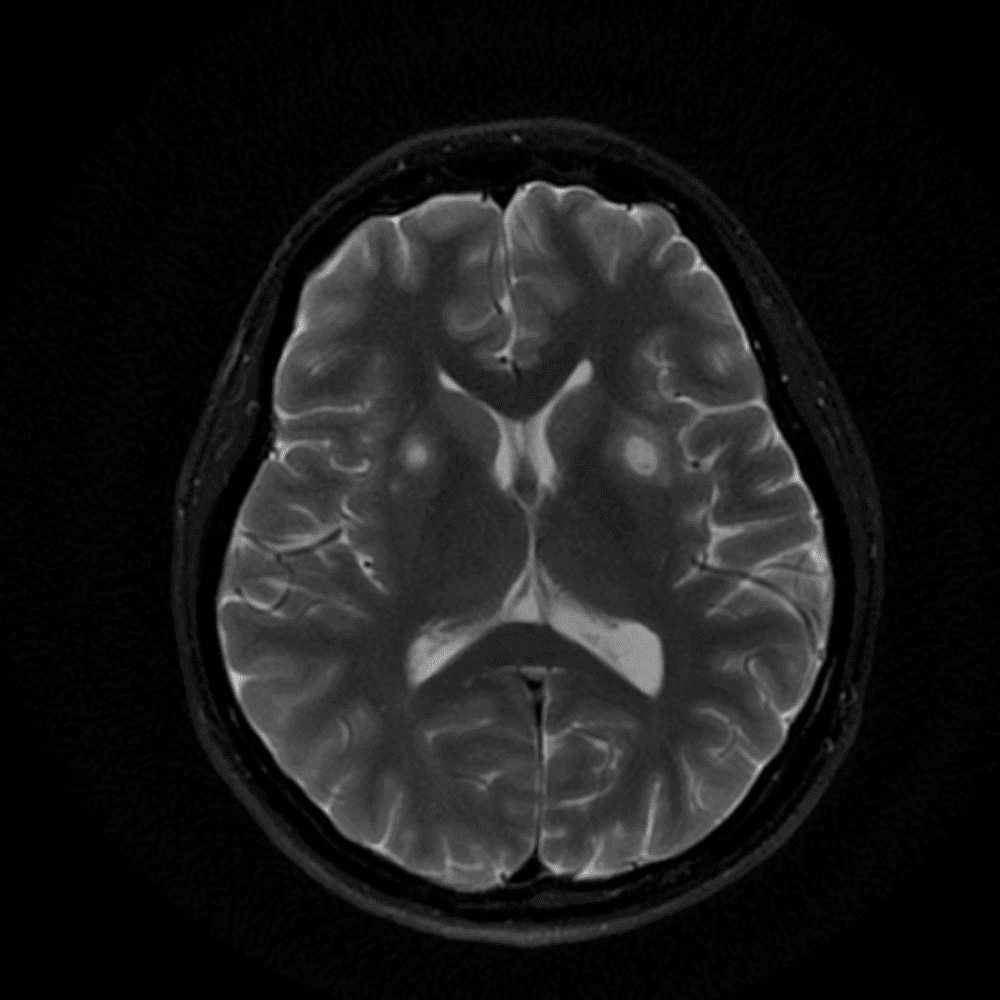

๋‹น์ง ์‹œ ํ”ํžˆ ๋ณผ ์ˆ˜ ์žˆ๋Š” ์‚ฌ๋ก€์˜ ์ „ํ˜•์ ์ธ ์˜ˆ๋ฅผ ํฌํ•จํ•ฉ๋‹ˆ๋‹ค.

39 ์‚ฌ๋ก€

์—ฐ์Šต

๋ฏธ๋ฌ˜ํ•˜๊ฑฐ๋‚˜ ์–ด๋ ค์šด ์‚ฌ๋ก€์™€ ์ผ๋ถ€ ์ •์ƒ ์‚ฌ๋ก€๋ฅผ ํฌํ•จํ•˜์—ฌ ๋‹น์ง์„ ์‹œ๋ฎฌ๋ ˆ์ด์…˜ํ•ฉ๋‹ˆ๋‹ค.

50 ์‚ฌ๋ก€